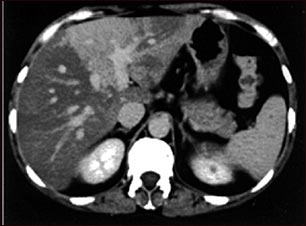

TC de hígado con exceso de grasa

Esta es una TC del abdomen superior que muestra esteatosis desproporcionada del hígado (hígado graso).